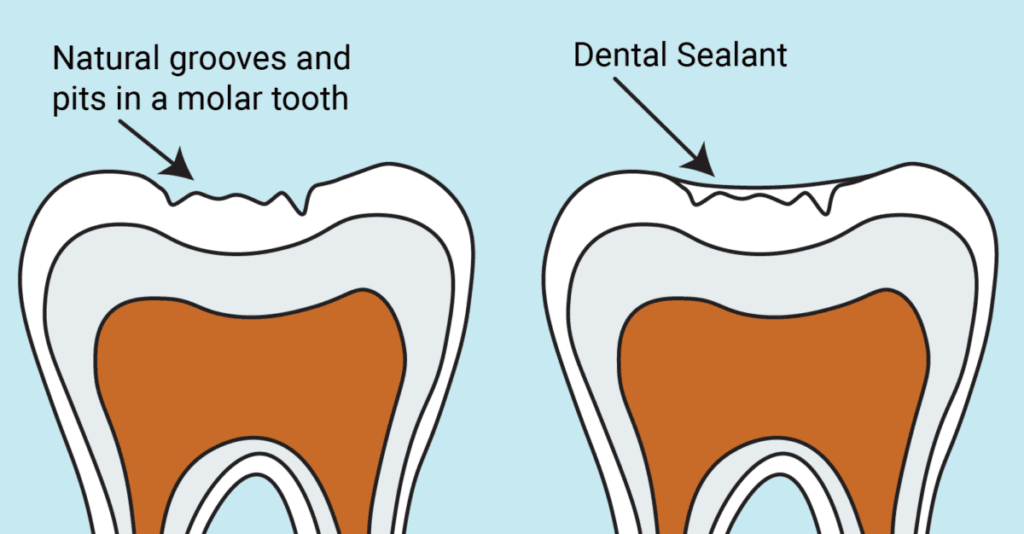

Dental fissure sealants, often simply called “sealants,” are thin, invisible plastic resin coatings applied to the chewing surfaces of teeth to help prevent tooth decay. They are most commonly placed on premolars and molars—the back teeth.Sealants flow into the natural pits and grooves of the teeth and then harden, forming a protective shield over the tooth enamel. The procedure is painless and highly effective in preventing decay. Studies show that fissure sealants can reduce the risk of cavities in permanent molars by up to 80%.

As teeth develop, deep pits, fissures, and grooves can form on the chewing surface. These pits and fissures are the areas most likely to develop cavities, especially in children, accounting for more than 50% of decay in kids.The deep grooves on the biting surface are called fissures, and the points where these grooves intersect are called pits. Pits and fissures are a natural part of tooth anatomy and vary in shape and depth. These deep areas are ideal places for food particles and dental plaque to accumulate.Toothbrush bristles are often too thick to effectively clean these tiny, narrow spaces. As food debris and bacteria build up, decay is more likely to develop. Enamel in pits and fissures also tends to be thinner and weaker, which further increases the risk of cavities. Once decay has formed and a cavity is present, the dentist must restore the tooth, and a pit and fissure sealant can no longer be placed on that area.

Compared with other teeth that may have shallower grooves, molars typically have deeper pits and fissures. Food particles easily get trapped in these areas, and sometimes toothbrushes cannot clean them effectively. This trapped food leads to plaque buildup and bacterial growth. Sealants help prevent decay in these areas by creating a smooth, protective barrier over them.